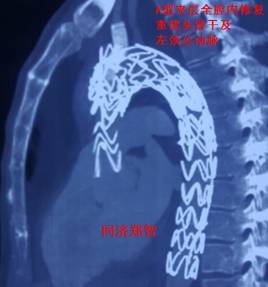

杀手锏终极*器武**了:A型夹层全腔内微创治疗。腔内微创治疗累及到升主动和主动脉弓的夹层一直是医学界的难题和挑战,这个技术属于临床初级阶段,还不完善,只适用于极少部分病人,是指结合开窗技术、烟囱支架技术等重建升主动脉和主动脉弓分支的技术(图16)。

(图16)